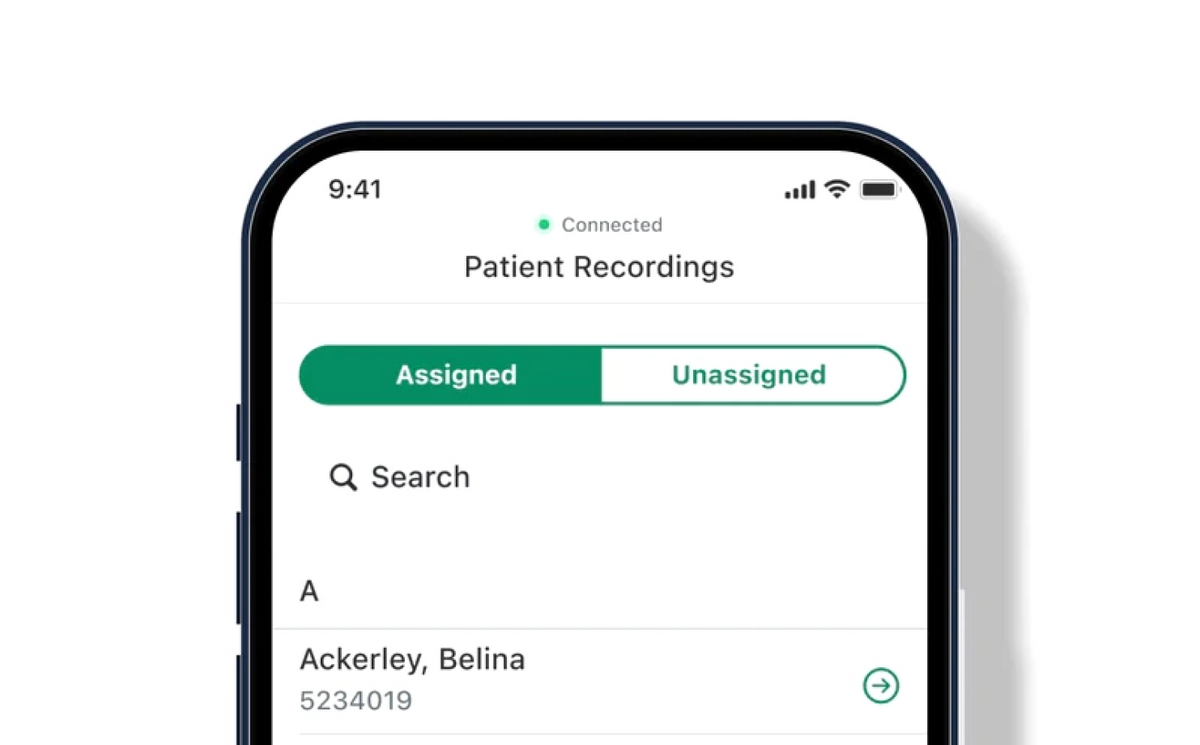

Save and share patient records.

Pair with the Eko App to save admin time, share data with colleagues, upload to your EMR, revisit past exam results, and monitor progress all while maintaining HIPAA compliance.